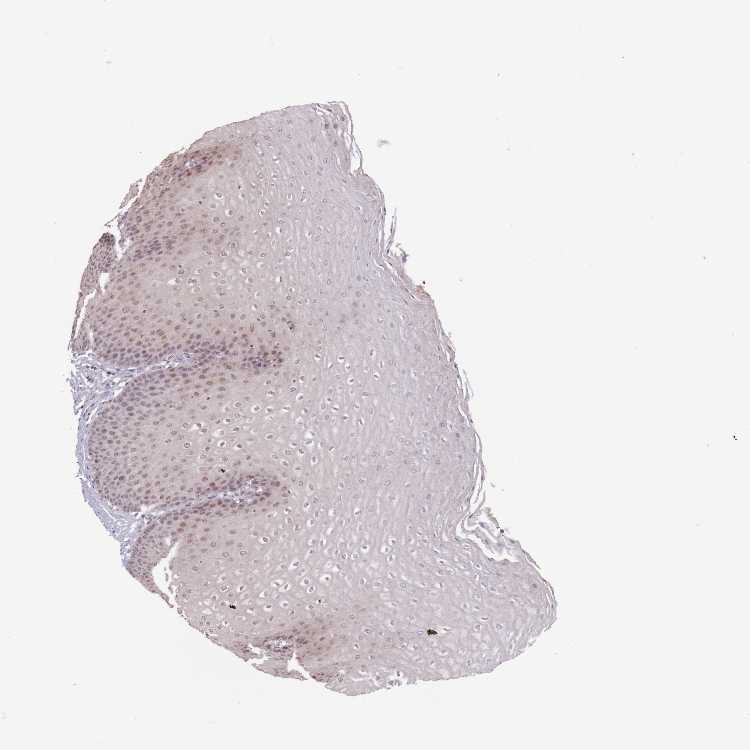

ESOPHAGUS - Antibody stainingi

Antibody staining in the annotated cell types in the current human tissue is reported as not detected, low, medium, or high, based on conventional immunohistochemistry profiling in selected tissues. This score is based on the combination of the staining intensity and fraction of stained cells.

Each image is clickable and will lead to virtual microscopy that enables deeper exploration of all samples and also displays staining intensity scores, fraction scores and subcellular localization as well as patient and tissue information for each sample.

Antibody HPA020387

Squamous epithelial cells Medium